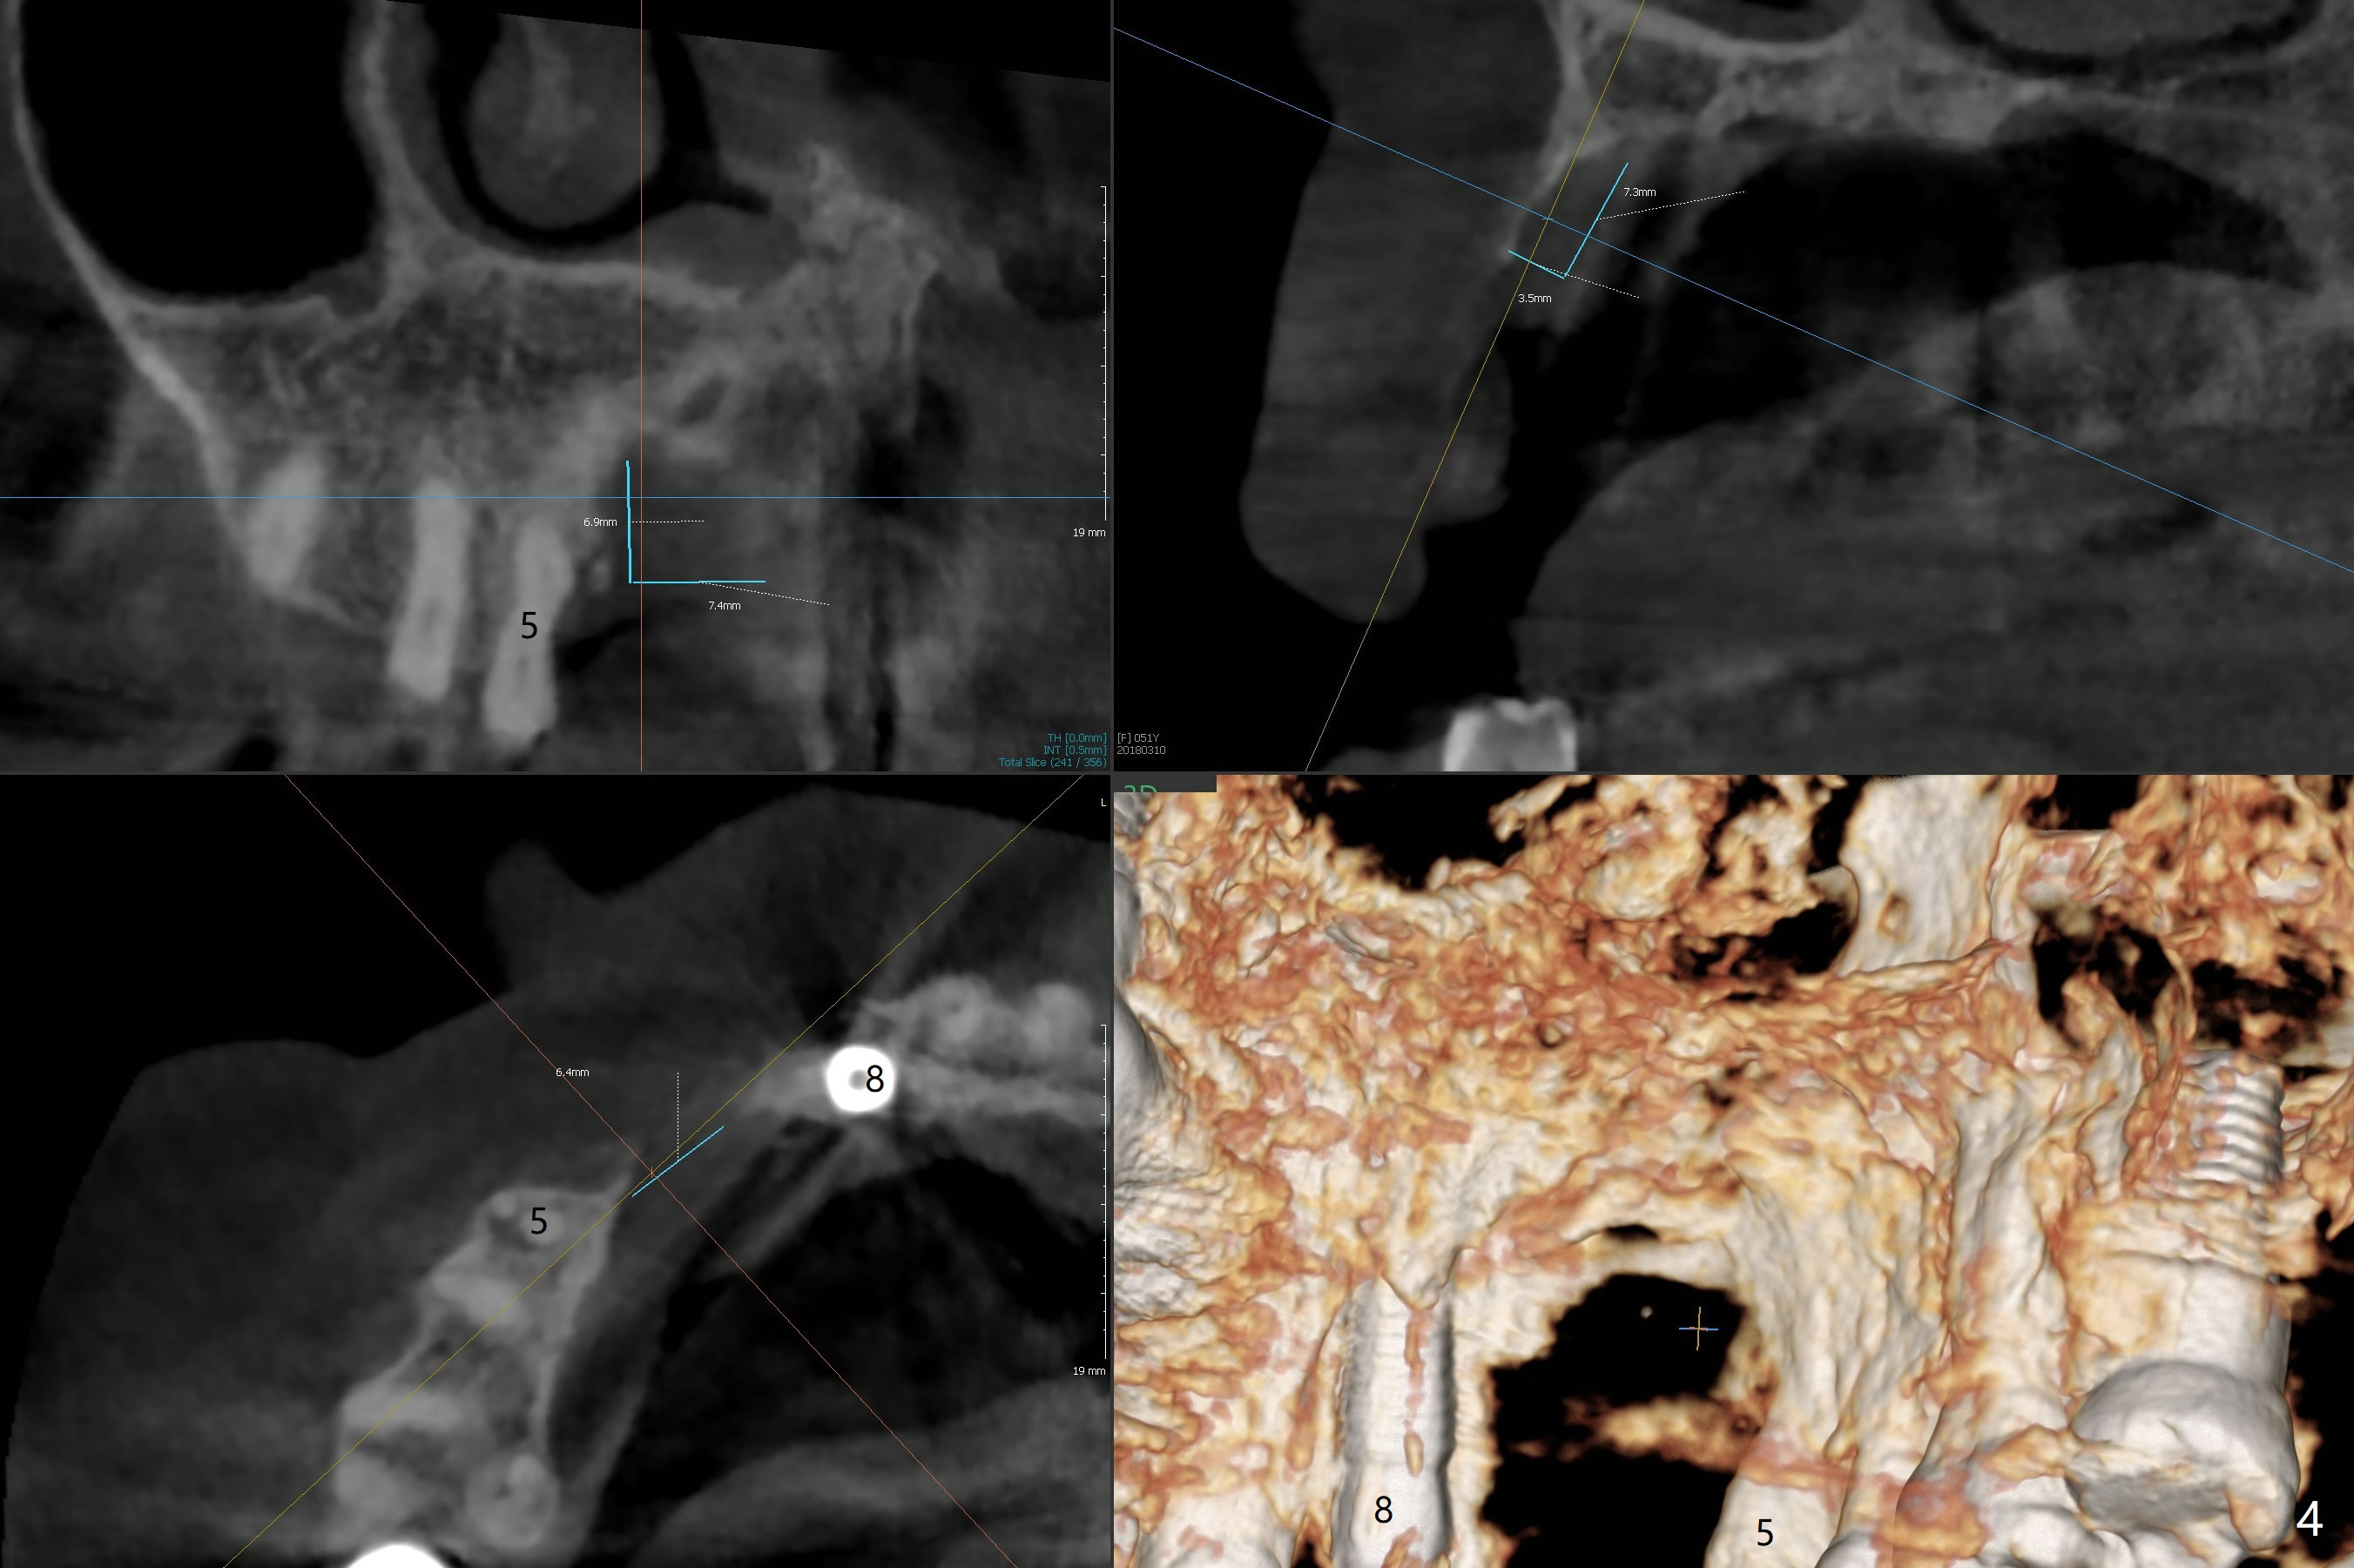

A 51-year-old woman lost the teeth #6 and 7 due to odontoma removal ~30 years ago. The area was restored with a FPD. The latter is removed with immediate implant at #8 8-9 months earlier. Particulate bone graft does not repair the bone deficiency at #6, 7 (Fig.2,3), although the soft tissue looks bulky (Fig.1). It appears that the palatal defect also needs a piece of bone block to fill in (Fig.4). The block will be harvested from the chin (Fig.5,6). If the block graft turns out to be impracticable, the periodontally compromised tooth #5 (bone loss, Fig.2,3,7) will be extracted for immediate implant. Initial osteotomy will be established in the palatal socket (Fig.8,9). Either a 2- (Fig.10) or 1- (Fig.11) piece implant will be placed. After wound healing, impression will be taken for a lab-fabricated provisional FPD.

An asymptomatic erythema develops at #8 10 months postop (Fig.12 *). A fistula forms 11 months postop (Fig.13 < ) and is associated with implant thread exposure (Fig. 14 >, as compared to Fig.2). It appears that bone graft and possible block graft are needed with PRF after debridement with Titanium brush.